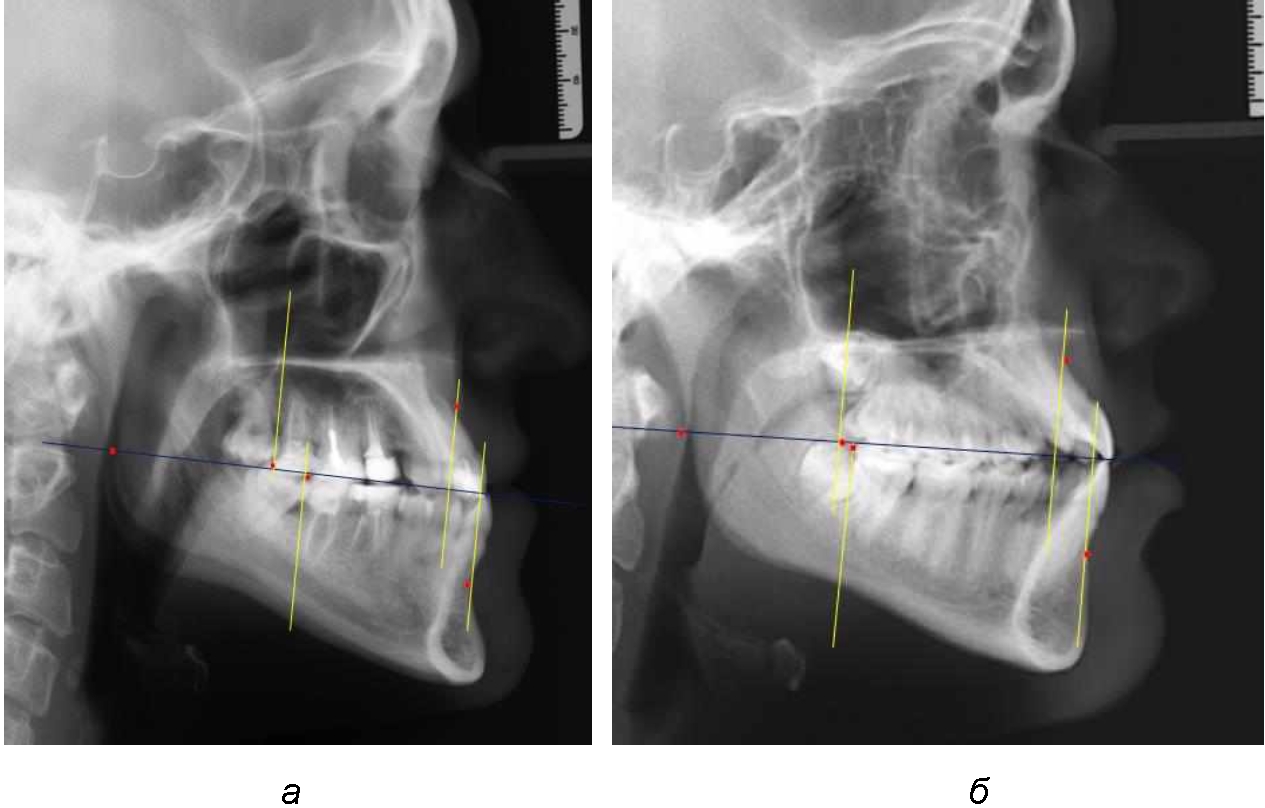

Аналогичное расстояние было отмечено и при расположении дистальных окклюзионных точек верхней и нижней челюсти (рис. 2).

Рис. 2. Положение апикальных точек и челюстей при нормопозиции (а), антепозиции (б) и ретропозиции (в) верхней челюсти

При анализе рентгенограмм, было отмечено, что на 26 снимках из 58 [(44,83 ± 6,53) %] отмечалась нормопозиция верхней челюсти. При этом средняя величина лицевого угла (ANSe) составила (85,04 ± 0,56)°, и пациенты были отнесены к 1-й группе 1-й подгруппе. Антепозиция верхней челюсти была отмечена на 20 те-лерентгенограммах [(34,483 ± 6,24) %], при этом величина лицевого угла составляла (89,12 ± 0,62)°. Ретропозиция была отмечена на 12 рентгенограммах [(20,69 ± 5,32) %], а средняя величина лицевого угла составляла (80,21 ± 0,48)°.

При всех вариантах положения верхней челюсти, было отмечено, что альвеолярно-денталь-ные размеры верхних зубо-челюстных дуг были близки по значению к аналогичным размерам нижней челюсти и разница в размерах не превышала 1,0–1,5 мм, а средняя величина различия показателей составляла (1,07 ± 0,54) мм.

Расстояние от конструируемой точки окклюзионной плоскости на ветви челюсти («rmРOcP») до апикальных точек Downs на обеих челюстях также коррелировало между собой, и средняя величина различия показателей составляла (1,23 ± 0,69) мм. Проекция нижней апикальной точки на окклюзионную линию, как правило, располагалась несколько кпереди проекции верхней апикальной точки, на величину около 1 мм, что соответствовало оптимальным данным Wits-анализа.